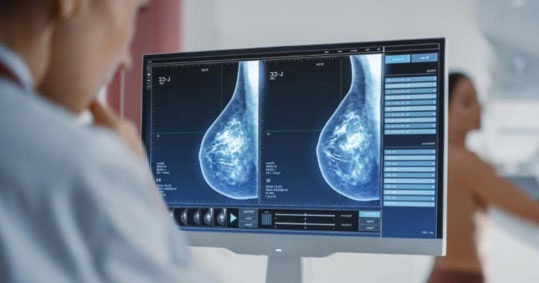

Τι σημαίνει ο πυκνός μαστός και πως συνδέεται με τον καρκίνο;

Γνωρίζετε πόσο πυκνοί είναι οι μαστοί σας; Το ερώτημα δεν είναι ρητορικό, αλλά έχει μεγάλη σημασία διότι η πυκνότητα των μαστών παίζει ρόλο στην ανάπτυξη καρκίνου.

Κατ’ αρχάς, ο πυκνός μαστικός ιστός μπορεί να «κρύψει» μικρές μάζες στη μαστογραφία.

Αυτό συμβαίνει διότι ο ινώδης ιστός απεικονίζεται ως λευκές/υπόλευκες περιοχές στην μαστογραφία.

Με τον ίδιο τρόπο, όμως, απεικονίζονται και οι μικροί όγκοι και αλλοιώσεις. Το γεγονός αυτό δυσκολεύει τον διαχωρισμό των ύποπτων αλλοιώσεων από τις καλοήθεις.

Αντιθέτως, ο λιπώδης ιστός τείνει να αποτυπώνεται ως σκουρόχρωμη περιοχή στην μαστογραφία.